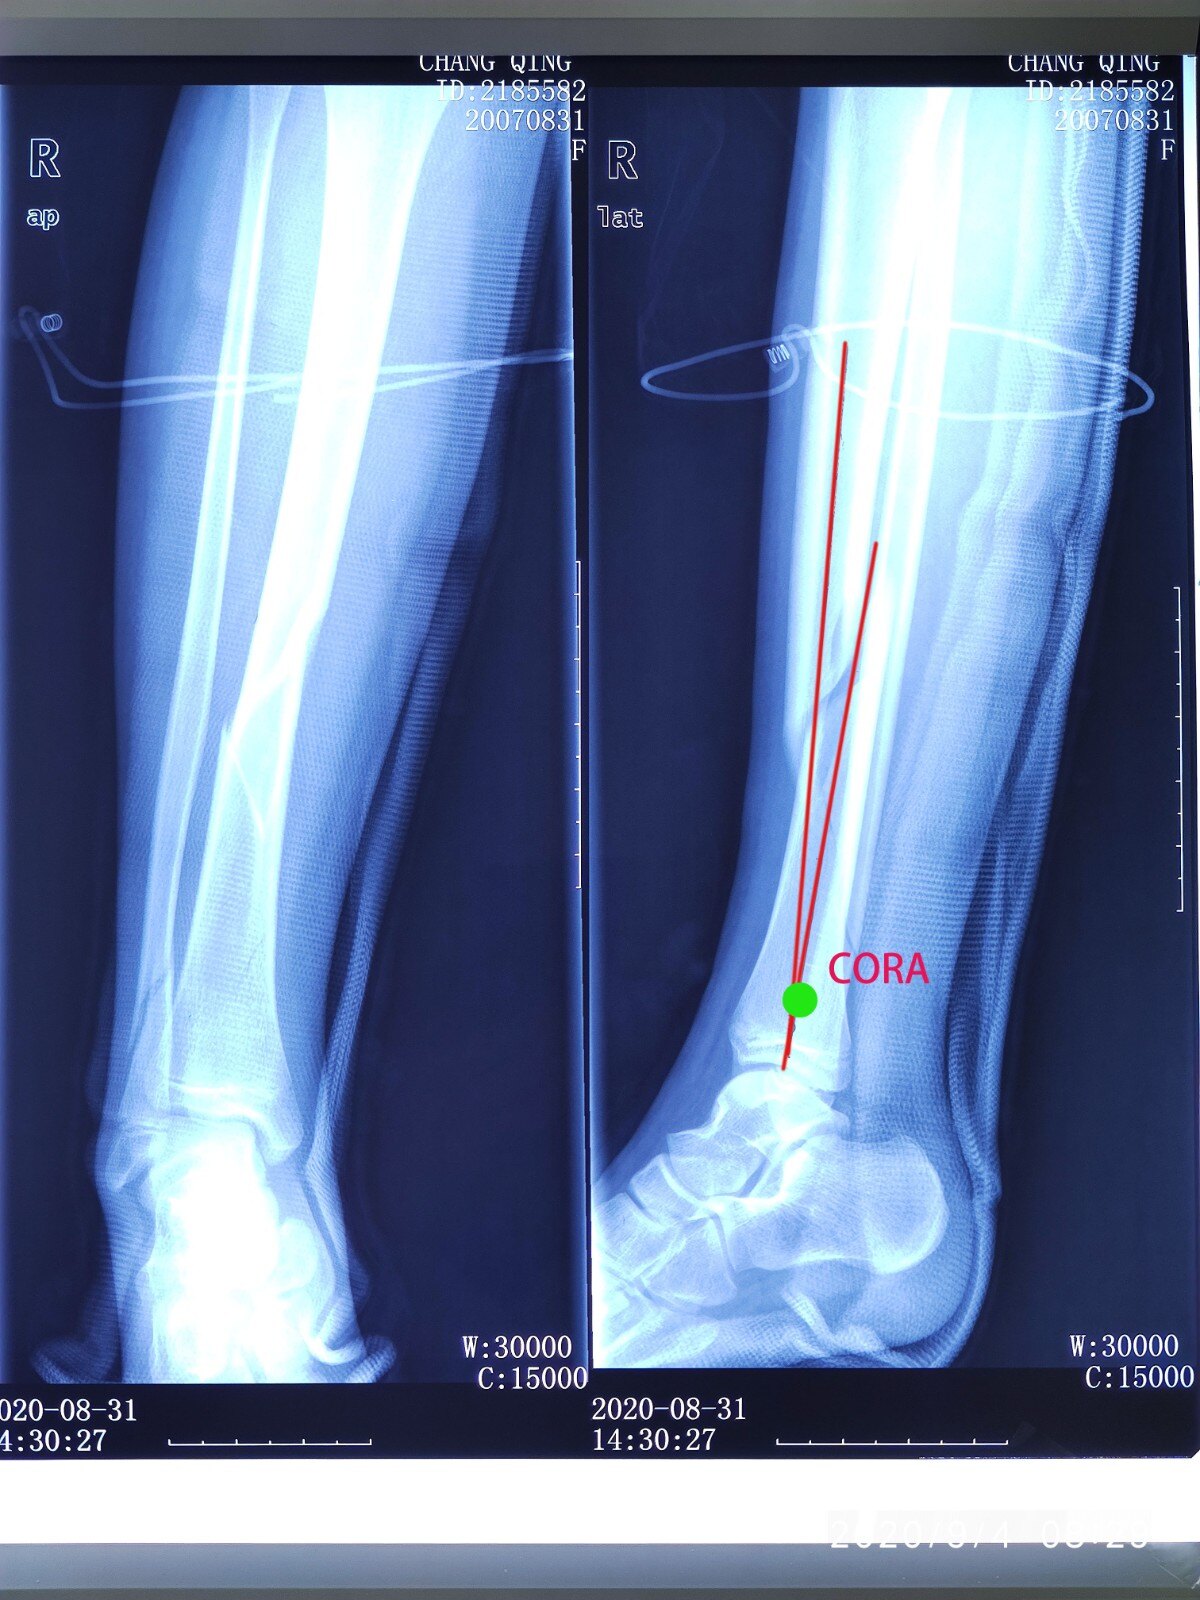

胫骨中段骨折最优内固定 髓内钉还是钢板 好医术早读文章 好医术 赋能医生守护生命

脛骨骨幹骨折 手術

脛骨骨幹骨折 手術-脛腓骨骨幹骨折症狀 1症狀 脛腓骨骨折多為外傷所致,如撞傷,壓傷,扭傷或高處墜落傷等,傷肢疼痛並出現腫脹,畸形等。 脛骨的位置表淺,局部症狀明顯,在重視骨折本身症狀的同時,還要重視軟組織 治療 脛骨遠位端骨折 (けいこつえんいたんこっせつ) では、その原因によってそれぞれ治療が異なります。 内果骨折 骨折部の偏位や脱臼による足関節の変形が著明でない場合には、ギプス固定などの保存的な治療を行います。 変形が著しい場合には、骨折部を整復してねじを刺入して変

脛骨骨幹骨折 手術のギャラリー